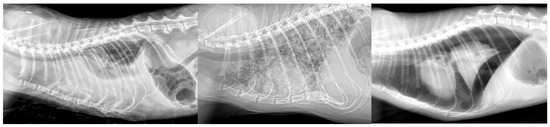

3.2. Results for Cats in Group R—Respiratory Origin

3.3. Results for Cats in Group C—Cardiac Origin

3.4. Results for Cats in Group T—Traumatic Origin

3.5. Results for the Cats in Group N—Neoplastic Origin